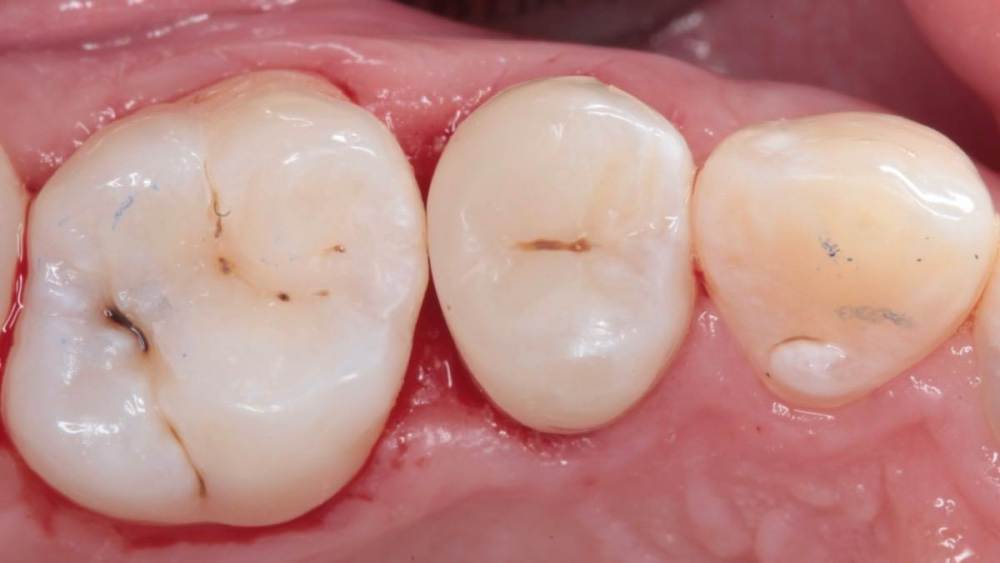

Гарриевич Опубликовано 21 мая, 2022 Поделиться Опубликовано 21 мая, 2022 (изменено) Будущее за регенеративной эндодонтией?) лечение в 2 посещения из-за нехватки времени (новый ассистент, перегруз пациентами, мысли о поднятии стоимости лечения, гипердиагностика?) глубокая пульпотомия, триоксидент, композит. фото подробно выложил это снимок с временной пломбой мало ли что вы подумаете Изменено 21 мая, 2022 пользователем Гарриевич 1 Ссылка на комментарий